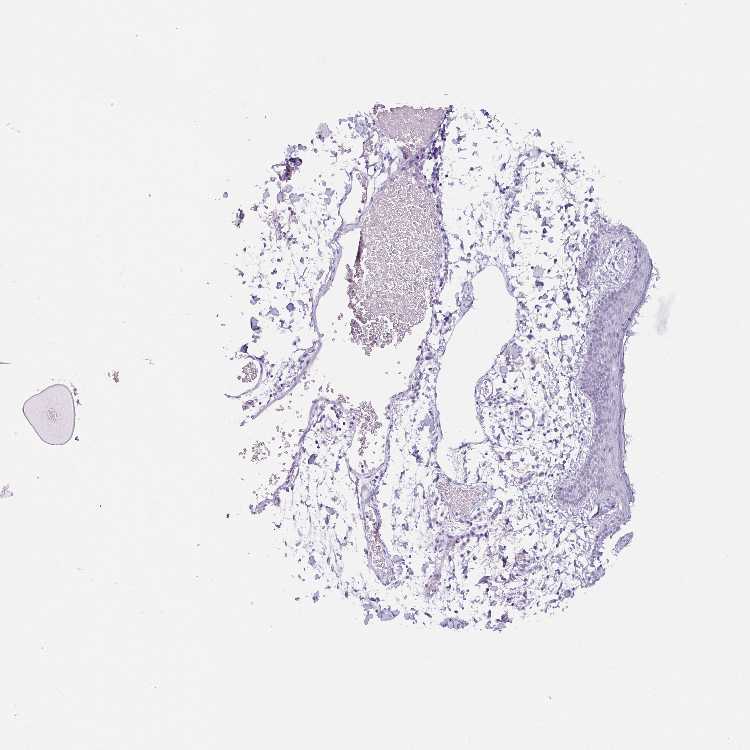

SKIN 1 - Antibody stainingi

Antibody staining in the annotated cell types in the current human tissue is reported as not detected, low, medium, or high, based on conventional immunohistochemistry profiling in selected tissues. This score is based on the combination of the staining intensity and fraction of stained cells.

Each image is clickable and will lead to virtual microscopy that enables deeper exploration of all samples and also displays staining intensity scores, fraction scores and subcellular localization as well as patient and tissue information for each sample.

Antibody HPA032081Antibody HPA032082Antibody CAB000016

Langerhans Not detectedNot detectedNot detected

Fibroblasts Not detectedNot detectedNot detected

Keratinocytes Not detectedNot detectedNot detected

Melanocytes Not detectedNot detectedNot detected

SKIN 2 - Antibody stainingi

Epidermal cells Not detectedNot detectedNot detected